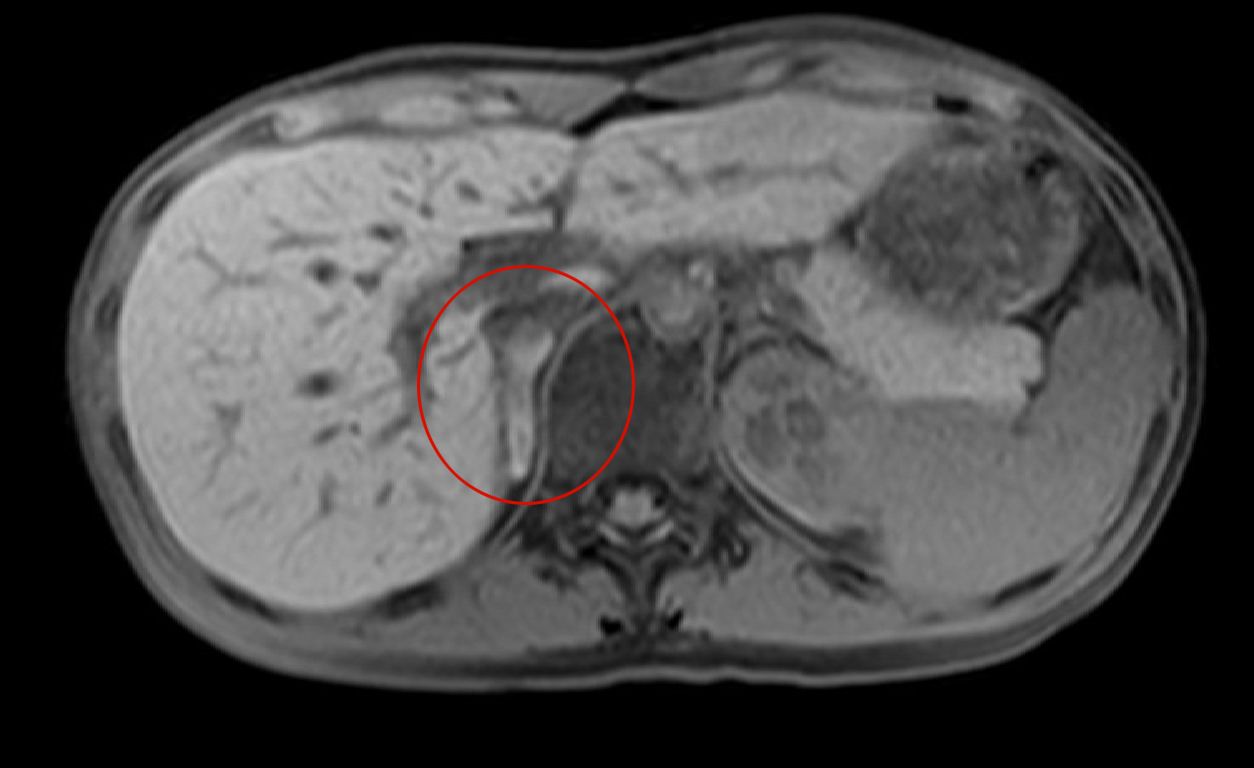

- 【3週間後 MRI 脂肪抑制T1WI】

-

- 右副腎脂肪抑制T1WIで高信号となっており副腎出血を疑う。

- 左副腎の腫大は改善